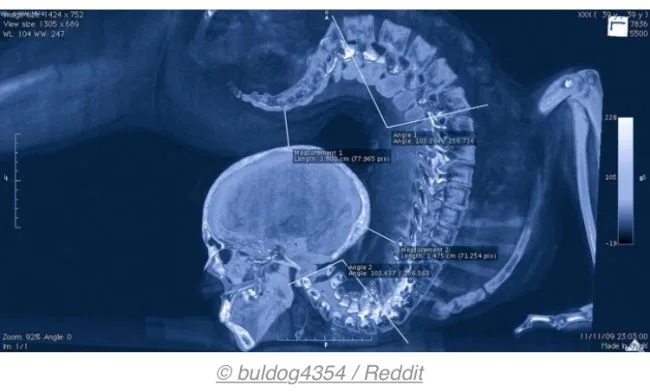

7 นี่เป็นภาพเอกซเรย์ (X-Ray) ของผู้ที่ทำท่าดัดร่างกายตัวเอง